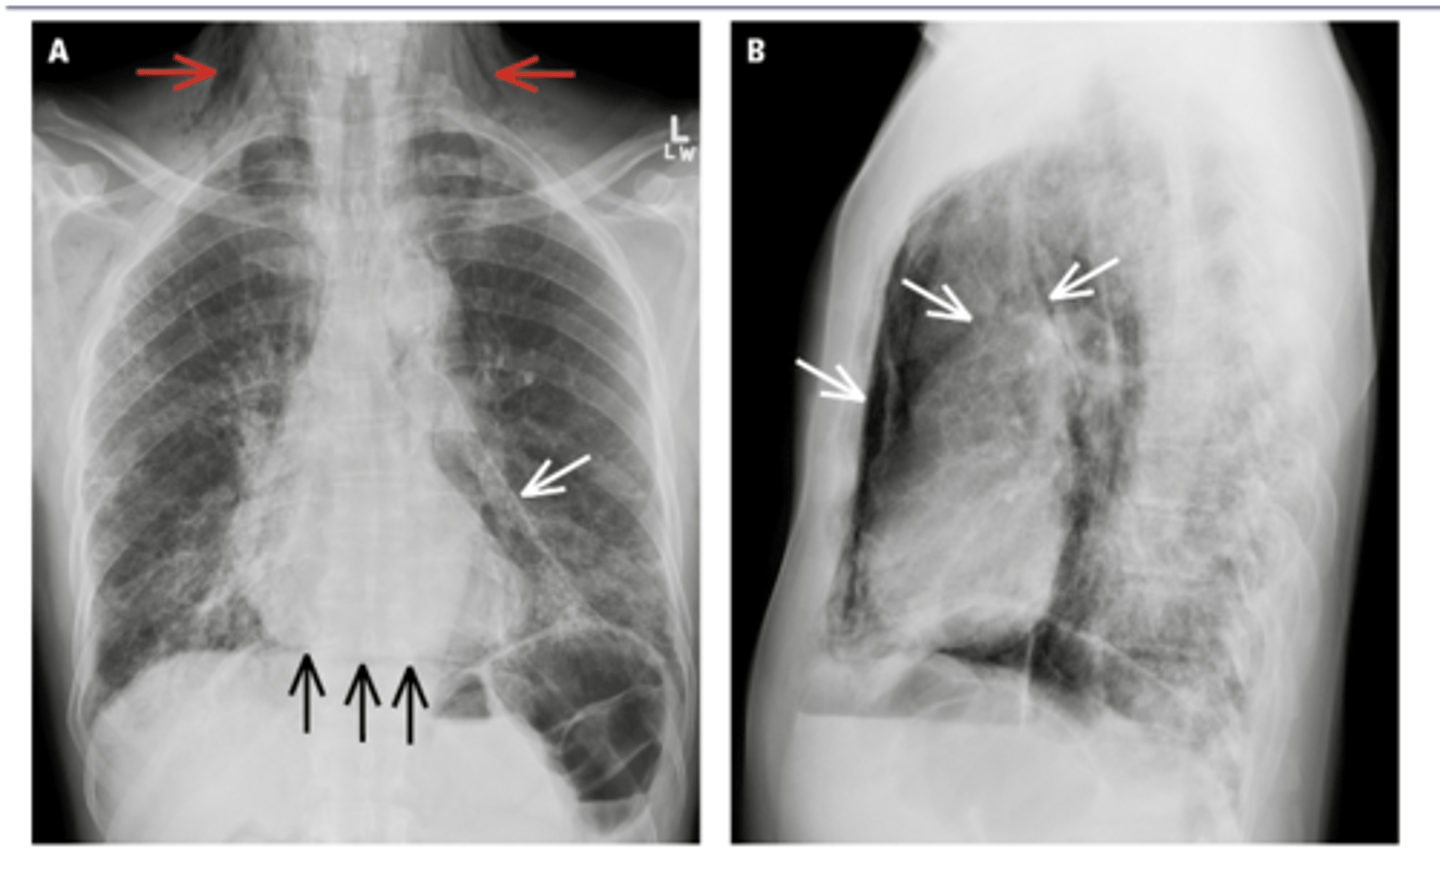

New cards

Pneumothorax (caused by stabbing)

visceral pleural line in the left chest (white arrows).

horizontal line along the base of the left hemithorax, which represents an air-fluid level (black arrows), showing that the patient has a hemopneumothorax.

2 key findings in this x-ray and dx

<p>2 key findings in this x-ray and dx</p>